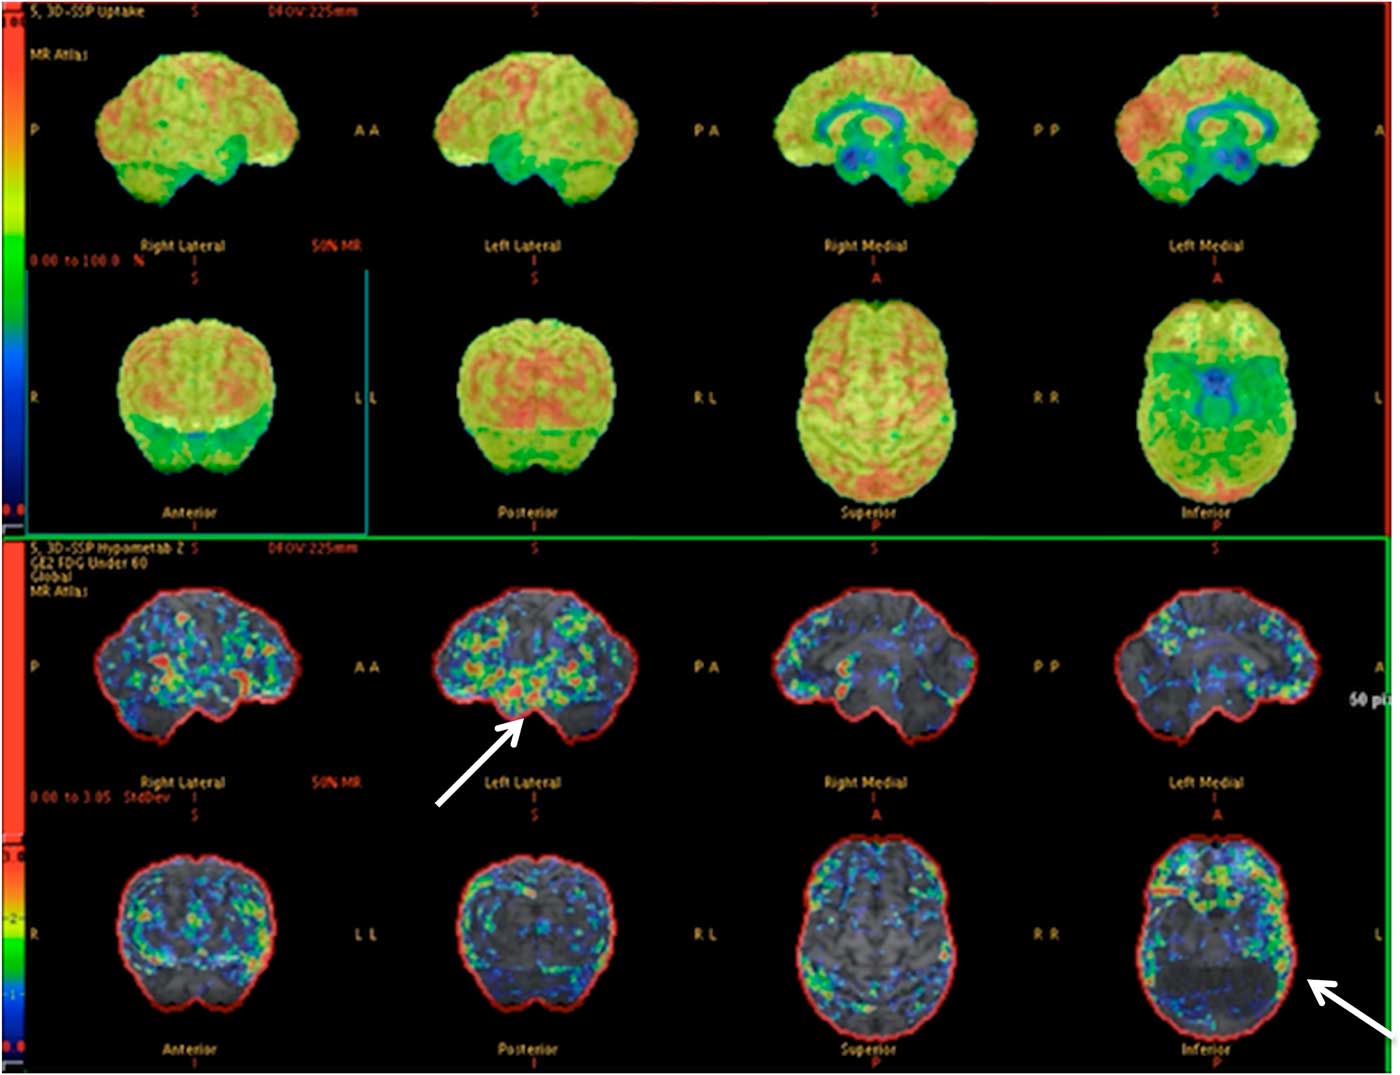

Of the 36 patients with vEEG and PET concordance, 17 (13 TLE, 4 eTLE) underwent surgical resection of the epileptogenic focus (47.2%), 7 TLE are awaiting surgical resection, 11 (7 TLE, 4 eTLE) were deemed ineligible for surgical resection due to multiple epileptogenic foci identified (an example is shown in Figure 1), and 1 TLE patient with concordant findings is awaiting further assessment with iEEG.

Figure 1 PET images depicting hypometabolism in the mesial aspect of both temporal lobes anteriorly. (Arrows) There is subtle asymmetry, with the right side being slightly more severely affected. The patient (57-year-old male) was deemed ineligible for surgical resection due to bitemporal involvement, which was also found on vEEG (normal MRI).